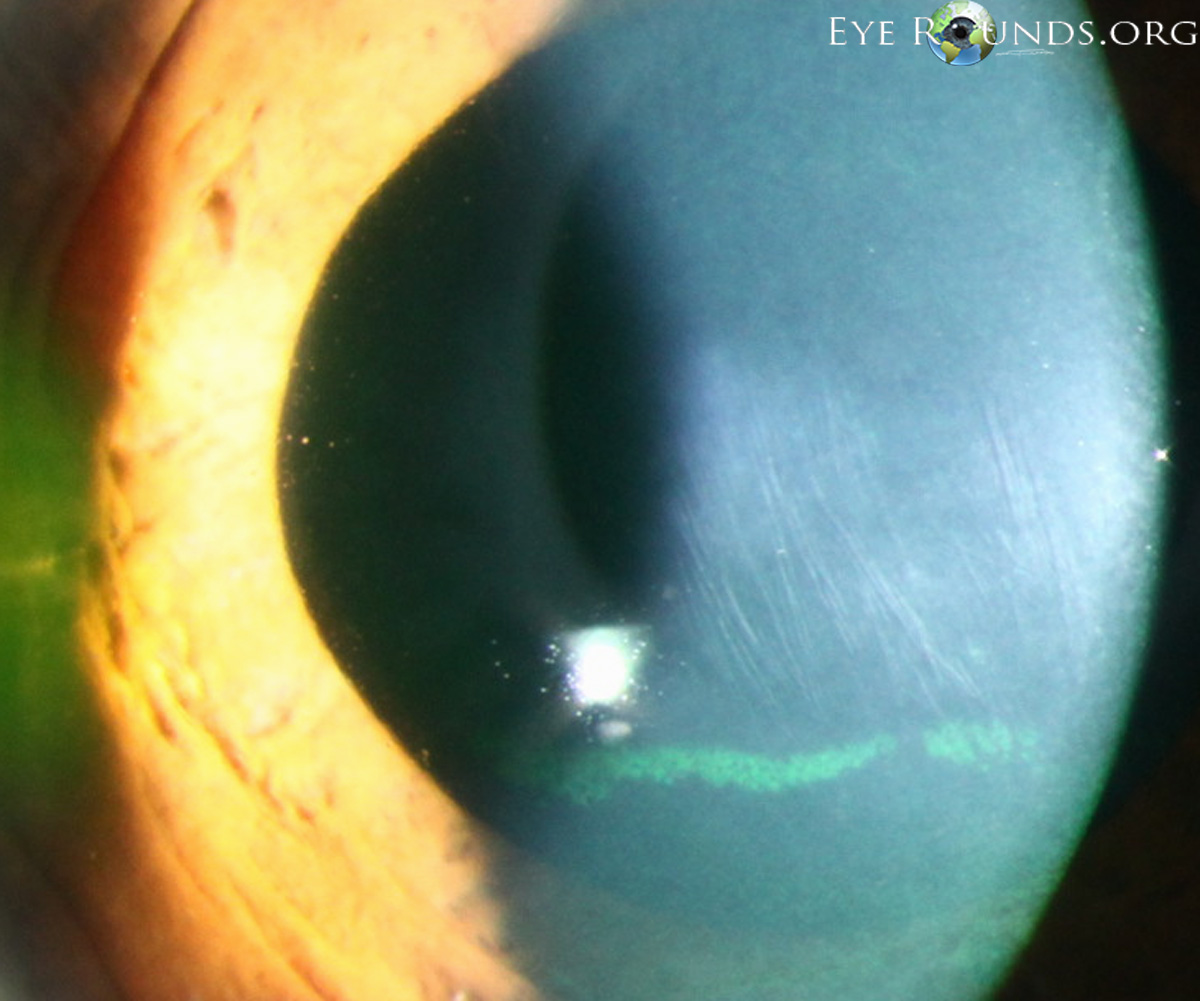

Vogt's Striae는 각막이 얇아지면서, 돌출되면서, 발생하는 기질의 긴장선, stress line 입니다.

데스메막 바로 앞쪽에 존재하는 각막 기질에 있는 여러개의 수직선입니다.

이는 각막이 흐물흐물해지면서 발생하게되는 선으로, 안압이 가해지면 사라집니다.

진단적으로 중요한 소견입니다..